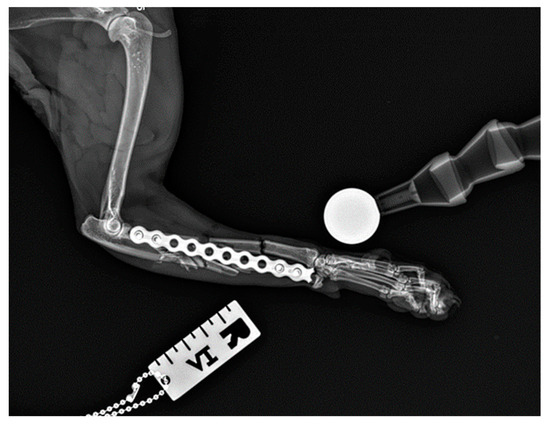

Figure 8. Postoperative lateral radiograph of the right antebrachium of a female domestic shorthaired cat. The plate was fixed by mistake to the proximal radius and distal ulna. The case was immediately revised using minimally invasive plate osteosynthesis approaches.

All fractures were classified as complex diaphyseal fractures of radius and ulna: 22-C2 or 22-C3 in the AO VET fracture classification system [24]. In 40 cases, the axial and rotational alignment of the joints above and below the fracture was appropriate and attachment of the main fracture fragments to the comminution zone was adequate. Location, placement, and the size of the implants were all assessed as correct on postoperative radiographs. In two cases (two right limbs), the plate was fixed by mistake to the proximal radius and distal ulna (Figure 8 because the distal approach was made between the lateral digital extensor tendon and the carpi ulnaris tendon, rather than between the extensor carpi radialis tendon and the common digital extensor tendon. After revision surgery and correct fixation of the radius, the alignment, adjacency, and apparatus were all satisfactory.